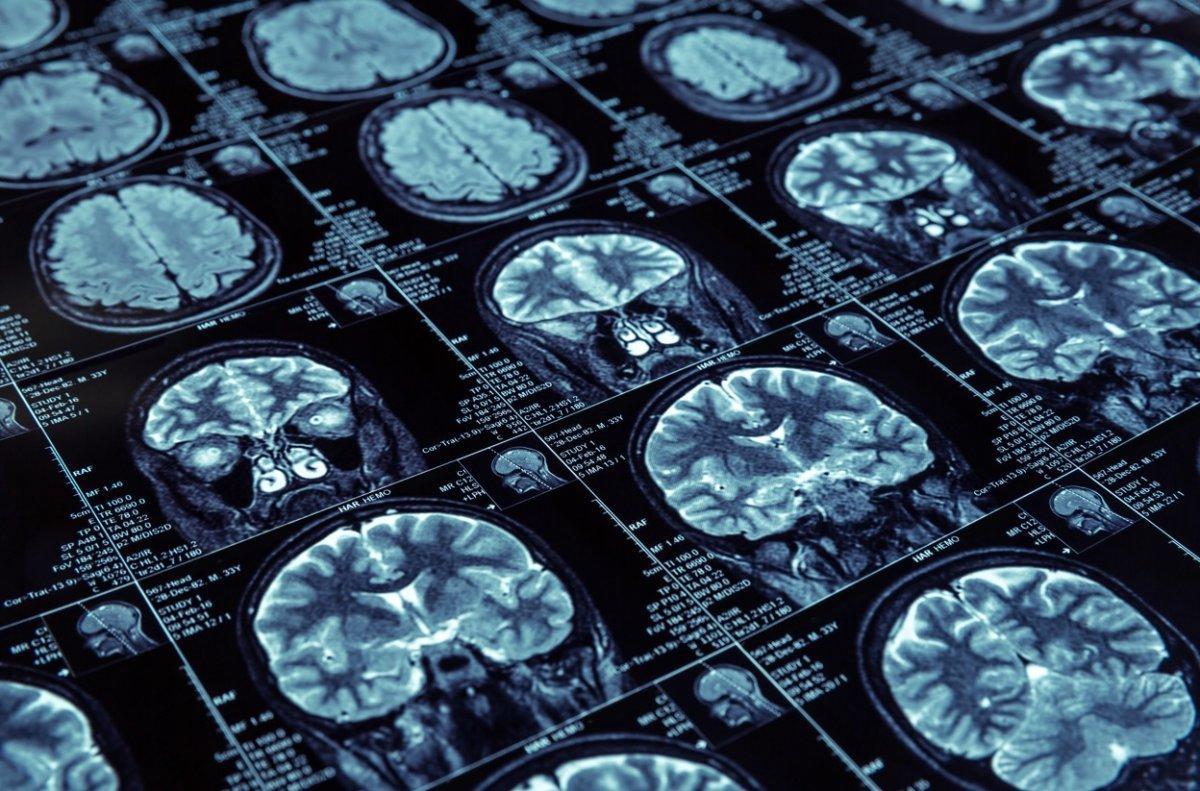

Kontrastlı veya kontrastsız bilgisayarlı tomografi, manyetik rezonans görüntüleme ve anjiyografi gibi görüntüleme testleri ile tanı konur. Yaklaşık 10 inme vakasından biri beyin kanamasından kaynaklanır.

Beyin kanaması teşhisi, beyin içinde kan varlığını gösteren kontrastlı veya kontrastsız manyetik rezonans görüntüleme, bilgisayarlı tomografi ve anjiyografi gibi görüntüleme testleri yapılarak konur.

Manyetik rezonans görüntüleme lezyon çevresindeki ödemin görülmesini sağlar ve bu sayede lezyonun derecesi bilinebilir. Bilgisayarlı tomografi ise hekimin kanama kontrolü yapabilmesi ve böylece hemorajik inmeyi iskemik inmeden ayırt edebilmesi açısından önemlidir.

Anjiyografi, damarların içinin görüntülenmesini kolaylaştıran tanı testidir ve örneğin anevrizmanın teşhisinin yanı sıra şekil bozukluğunun şekli, varlığı değerlendirilebilir.

Bununla birlikte, beyin kanaması olan bazı kişiler, MRI veya BT taramalarında normal sonuçlara sahiptir. Bu nedenle doktor beyin omurilik sıvısının çıkarılması olan lomber ponksiyon isteyebilir, çünkü beyin kanamasında beyin omurilik sıvısında kan vardır.